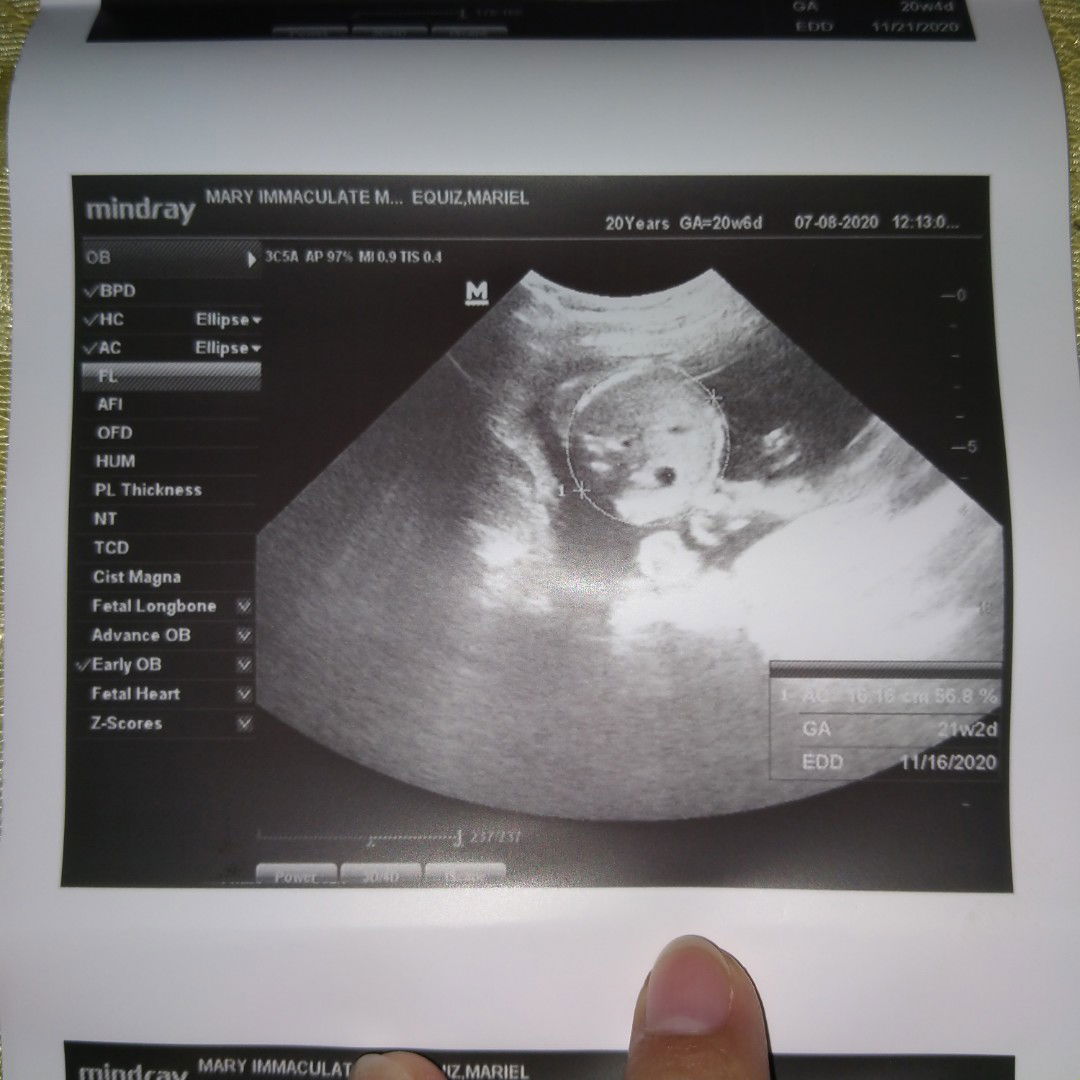

10weeks ako dinugo ako nung Saturday ng gabi agad ulit kami nagpacheck up at naadmit ako . Fresh blood nalabas sakin madalas sa Isang buwan mga 3-4x akong may bleeding. Naadmit ako yung pinakaunang ultrasound ko 7weeks sac palang Nakita tapos kahapon Monday nag request yung ob ko ng ultrasound dapat makita na si baby , laking gulat namin nung Nakita ko ultrasound na madaming parang sago sago ( bilog bilog) biglang Sabi ng ob ko kailangan ko agad maraspa dahil yung pinagbubuntis ko ay kiyawa or molar pregnancy ang tawag,di ko inexpect na ganto mangyayari sakin , grabe yung iyak disappoint ko bilang Isang nanay, yung inaalagaan ko at iniinuman ng vitamins ay Hindi pala baby, di ko alam kung bakit nangyayari sakin to , yung mga Oras na pinanghihinaan ka ng loob. Akala ko baby na talaga kasi grabe paglilihi ko , pag kahilo pagsusuka pagbaba ng BP ko , pagiging matamlay at ayaw masyadong kumain, iBang iba sa unang pregnancy ko😭😭 ang sakit #sharing